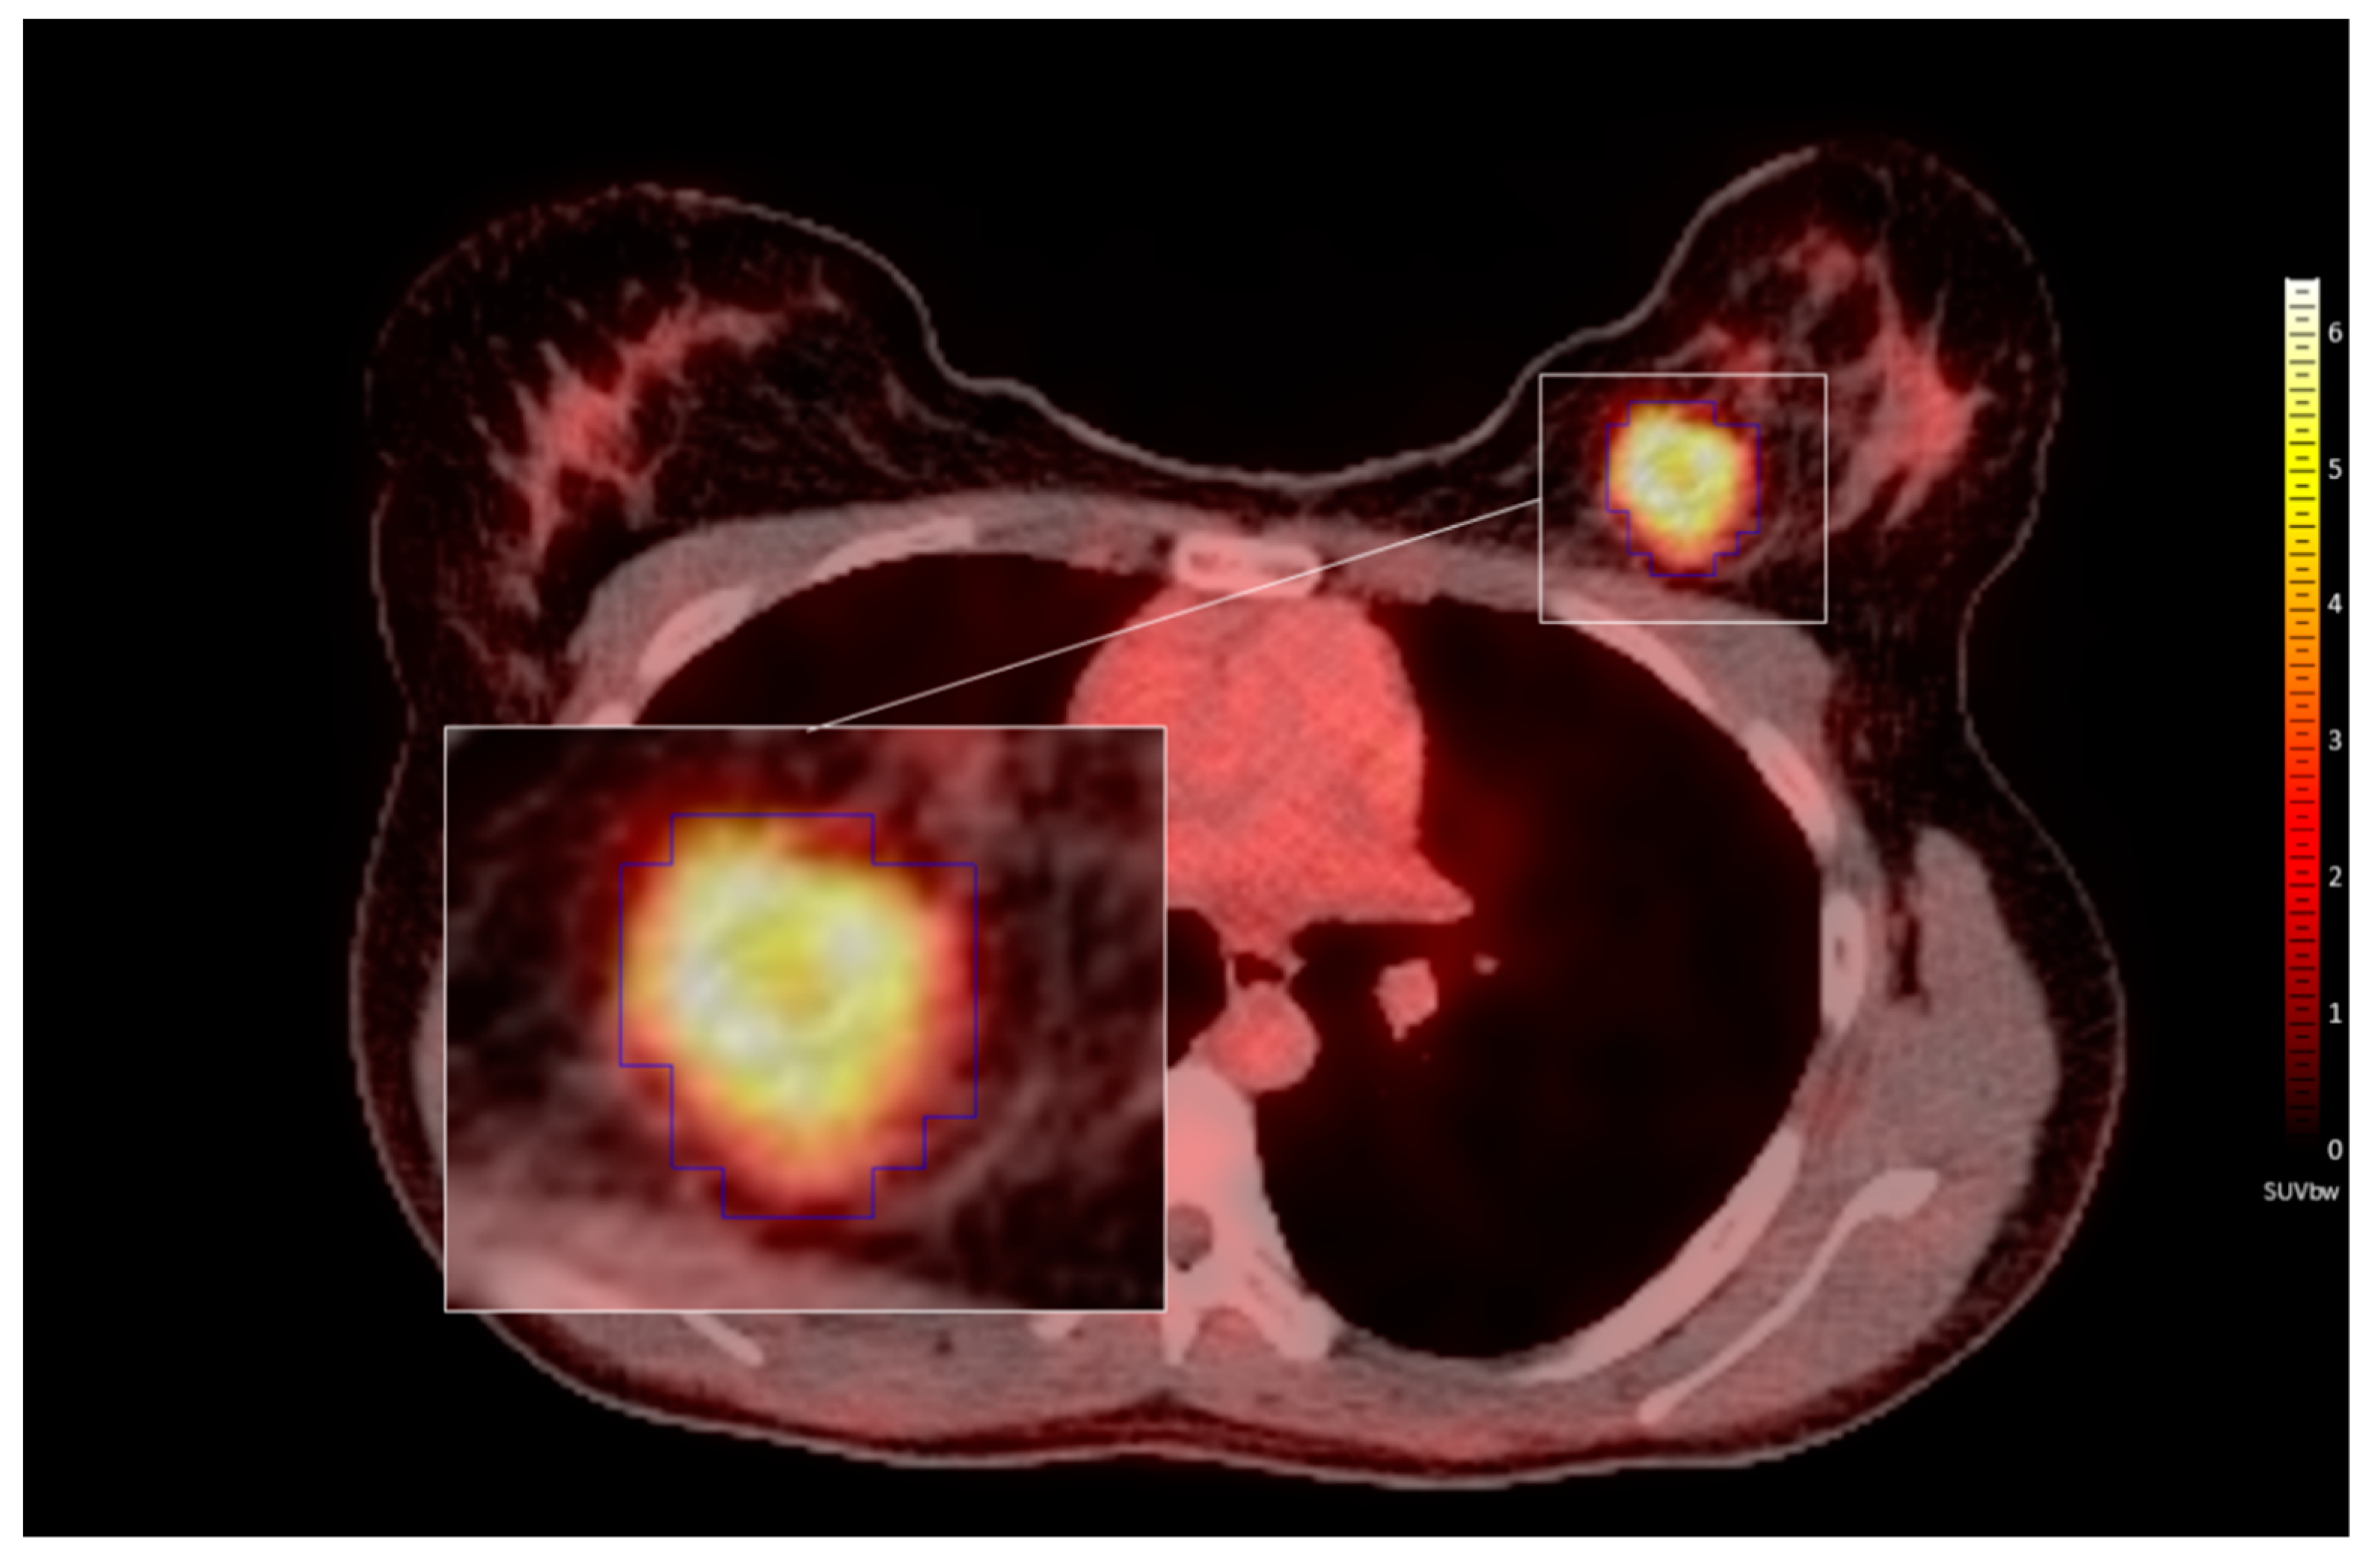

2.3. PET/CT

2.4. Lesion Delineation

2.5. Feature Extraction